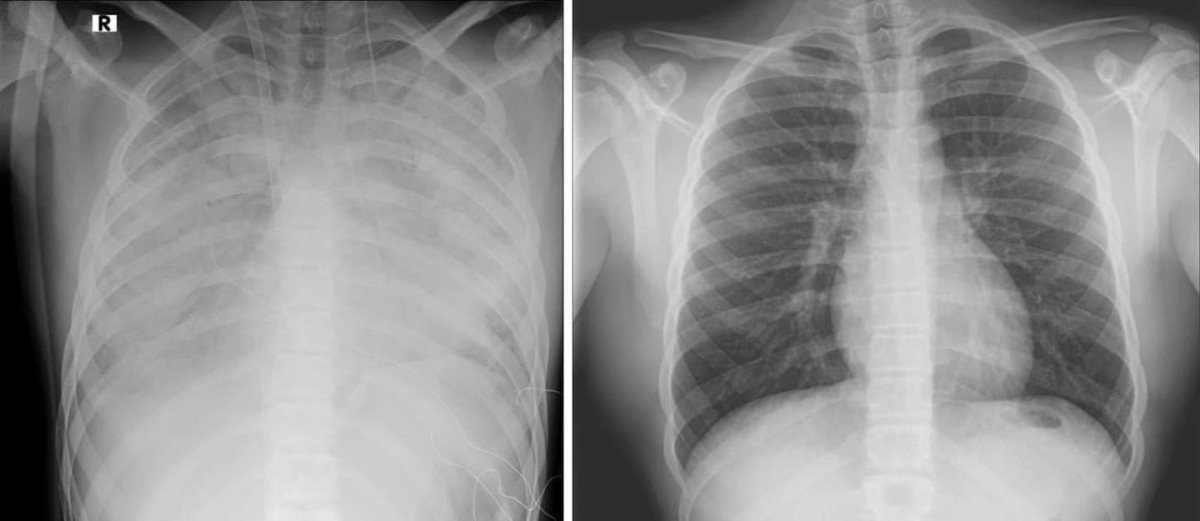

בתמונה: מימין צילום ריאות תקין, משמאל ריאותיו של הנערנער בן 16 מאושפז במרכז שניידר במצב קשה עם קריסה של הריאות לאחר שימוש בסיגריות אלקטרוניות. הנער הובהל ליחידה לטיפול נמרץ לב, שם הוא מאושפז בהכרה ומחובר למערכת האקמו, המחליפה את פעילות הלב והריאות - כך מפרסמים הבוקר כתבי אתר ויינט, רענן בן צור וגד ליאור.

הנער הועבר למרכז שניידר מבית החולים קפלן, לאחר שריאותיו קרסו. מבירור רפואי מקיף שערכו בבית החולים קפלן עלה כי מצבו הידרדר כתוצאה מעישון של סיגריות אלקטרוניות.

פרופ' עובדי דגן, מנהל היחידה לטיפול נמרץ לב בשניידר, מסר: "הנער התקבל ליחידה לטיפול נמרץ לב במצב קשה מאד כשריאותיו אינן מתפקדות, והוא זקוק לתמיכה מלאה של מכשיר אקמו. אנו מטפלים בו ומקווים מאוד לשיפור במצבו בימים הקרובים. הנזק שנגרם, ככל הנראה, מעישון של הסיגריות האלקטרוניות הוא נזק עצום. אנו קוראים לכל ההורים, מנעו את המקרה הבא".